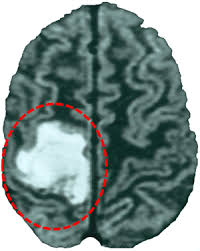

Una vez aprendido este comportamiento, se les practica una lesión por aspiración en la corteza motora contralateral a su mano preferente, de manera que, si es una rata diestra, se les lesiona el hemisferio izquierdo y, si es zurda, se le lesiona el hemisferio derecho, puesto que cada hemisferio cerebral controla la extremidad contraria. Tras comprobar que la lesión es efectiva, se procede a realizar trasplantes neurales.

Esta nueva fase consiste en aplicar la hormona de crecimiento combinada con rehabilitación a ratas adultas condicionadas para realizar el test de habilidad motora fina, lesionadas posteriormente por aspiración en la corteza motora y en las que se ha comprobado la efectividad de la lesión.

Para realizar los experimentos, se dividieron las ratas en varios grupos. A uno de ellos se le aplicó la hormona del crecimiento inmediatamente después de la lesión y a otro, a los seis días. El resultado, corroborado por otros grupos de animales que sirven de control para el experimento, es que las ratas del primer grupo alcanzaron una recuperación funcional del déficit motor y las del segundo no.